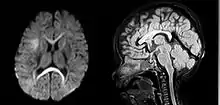

Мегаленцефалія та гемімегаленцефалія

Мегаленцефалія — це порушення розвитку при якому мозок має аномально великий розмір. Середня вага мозку на 2,5 стандартні відхилення перевищує середнє значення загальної сукупності[10]. Гемімегаленцефалія — надзвичайно рідкісна форма макроцефалії, що характеризується нерівномірним розвитком півкуль мозку (половина мозку більша за іншу)[11].